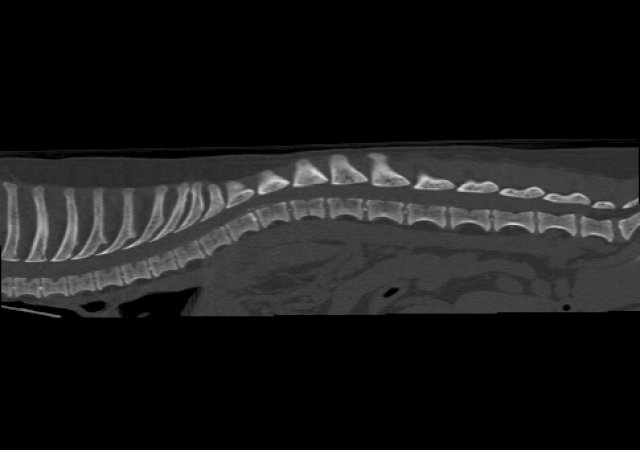

Bandscheibenvorfall (Diskopathie) und Lähmungen

Jeder Hund kann einen Bandscheibenvorfall bekommen, doch meist sind es die kleinen (chondrodystrophen) Hunderassen, wie beispielsweise Französische Bulldoggen, Dackel, oder Jack Russel Terrier, die zu uns kommen, weil sie schwankend laufen oder gar vollständig gelähmte Gliedmaßen haben. Gerade bei den gelähmten Patienten ist schnelles Handeln erforderlich. Für die Diagnose bietet unsere Praxis das unbedingt notwendige CT.

Nicht jeder Bandscheibenvorfall kann und muss operiert werden. Ist eine Operation notwendig, so ist es häufig die Operation mit einem Ventralslot (Halswirbelsäule), einer Hemilaminketomie (Brust- und Lendenwirbelsäule) oder einer dorsalen Laminektomie (Cauda Equina Compressionssyndrom).

CT Wirbelsäule